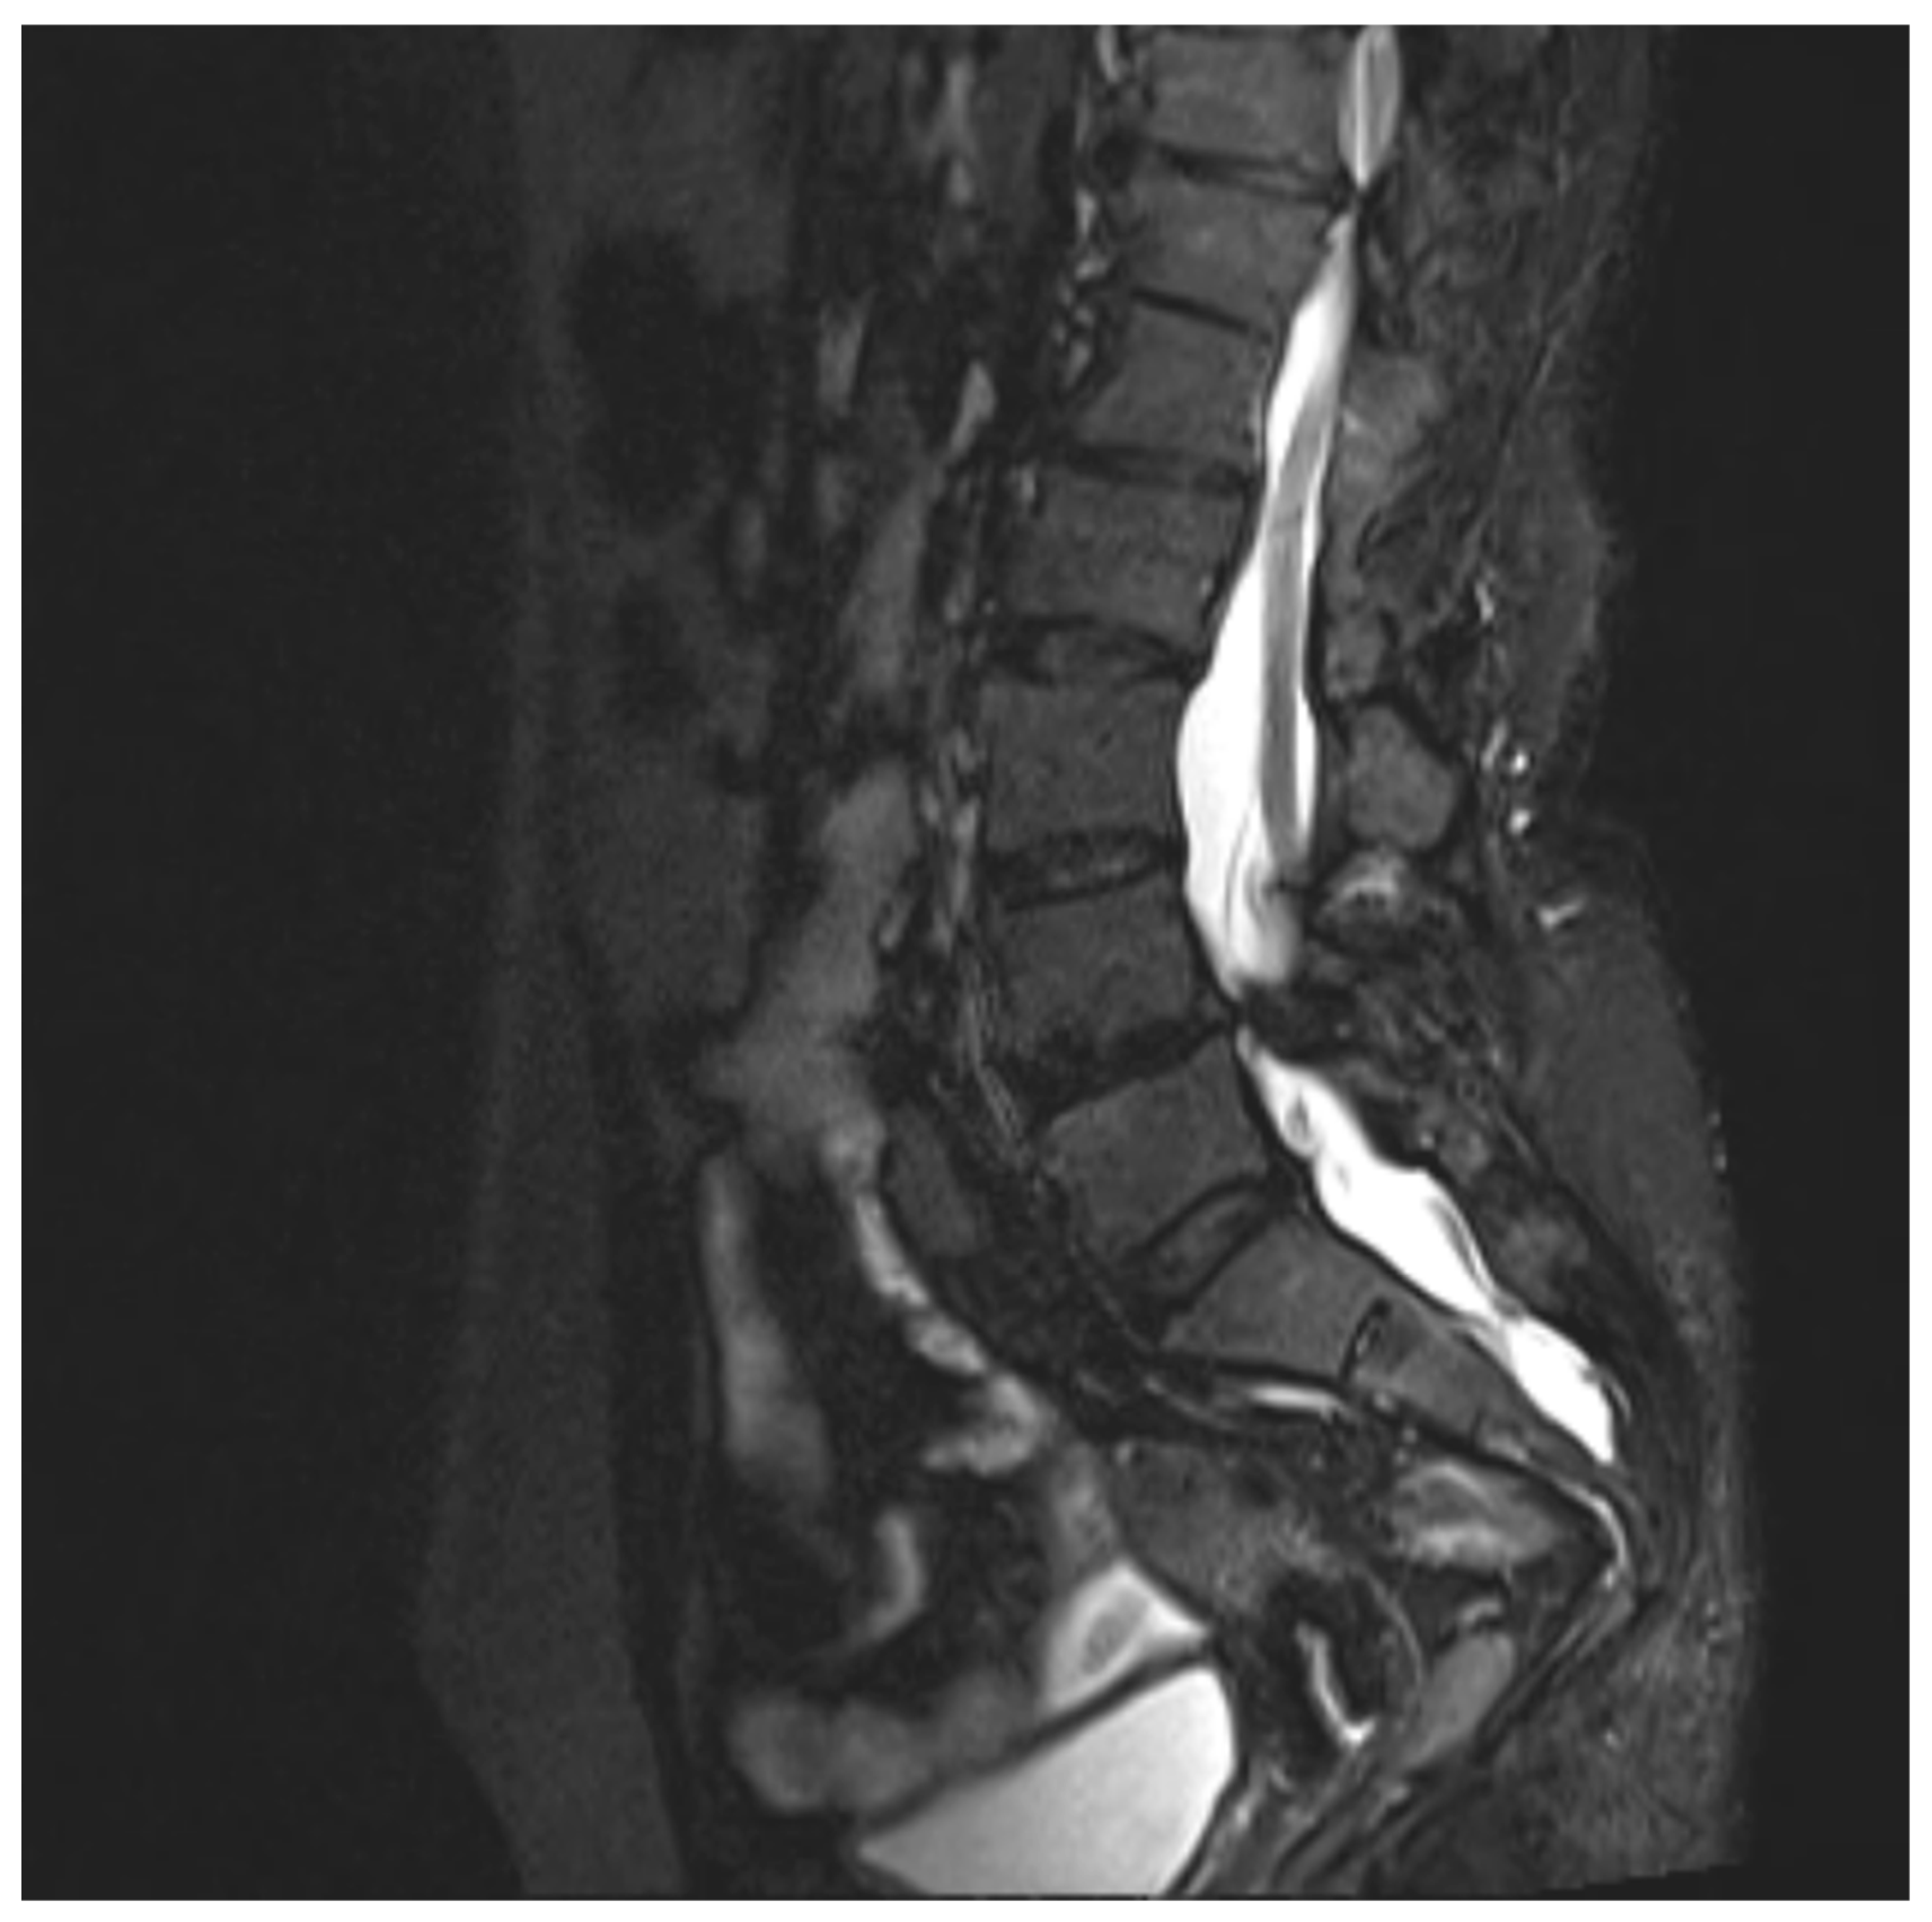

Figure 1. Sagittal MRI T2WI-STir image showing low lying tethered cord.

• Diastematomyelia (type 1) from D11-L4 vertebral level with tethered cord syndrome and spina bifida occulta present.

• Dural ectasia from D12 to S3 vertebral levels are seen.

• D10-D11 level: Diffuse disc bulge with ligamentum flavum hypertrophy causing effacement over anterior and posterior thecal sac, central canal stenosis and right neural foraminal narrowing with resultant mild compression over right exiting nerve root with evidence of intramedullary T2WI/STIR hyperintensity in the spinal cord, suggestive of compressive myelomalacia.